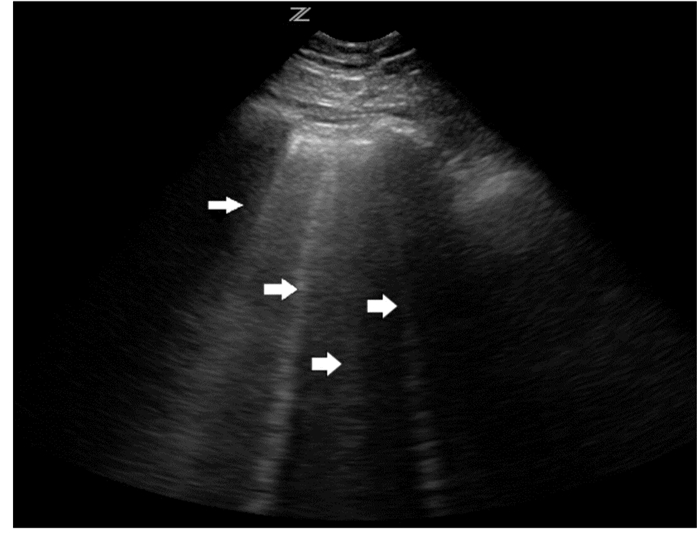

Ⅰ、Ⅱ两组患者的临床及超声参数见表 2。Ⅰ组和Ⅱ组患者在主动脉瓣根部内径、主肺动脉瓣环内径、左房、室间隔及左室后壁间无统计学差异(P>0.05),Ⅰ组患者B线总数、E/E’值及左室舒张末期内径均高于Ⅱ组,而EF值低于Ⅱ组,其差异有统计学意义(P < 0.05)。Ⅰ组肺超声检出的B线图像见图 1。Ⅰ组B线总数随纽约心功能分级变化的箱式图见图 2。

| 图 1 肺脏超声声像图示B线(箭头示) |

以往人们多认为超声不能应用于肺脏疾病的诊断,随着医学的不断进步,超声的应用范围越来越广泛,从而使得应用于肺脏疾病的诊断得以实现。Agricola等[6]首先提出了肺脏超声所检测出的B线能够鉴别心源性肺水肿和COPD急性加重,他所做的研究最终得出的结论是B线鉴别心源性呼吸困难的敏感度高达100%,特异度也可达到92%。Gargani[7]的临床研究也得到了相似的结果。B线实际上是一种混响伪像,其产生机制是超声在气体与水的交界处产生强烈的混响,声束产生无尽的反射,即超声在脏层胸膜与浅表肺泡之间的不断反射;表现为自胸膜发出垂直于胸膜并无限延伸至屏幕边缘的纵向激光样征象,如图 1。一般心源性因素引发的B线多为两侧对称性弥漫分布,ARDS、肺炎等疾病也可以观察到B线,但均不是对称性弥漫分布的。